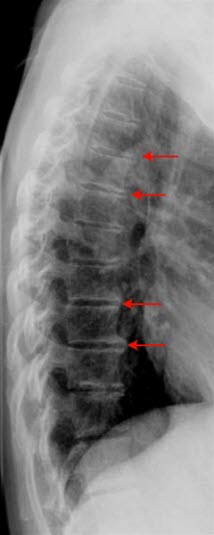

Diagnosen stilles ved hjelp av vanlige røntgenbilder av ryggraden. Man kan i mange tilfeller se at noen av mellomvirvelskivene er smalere enn normalt. Ofte kan en også se forkalkninger i ryggvirvlene eller i leddbåndene.

Spondylose er svært ofte et tilfeldig funn hos ellers friske individer. MR-undersøkelser av personer uten symptomer viser at cirka 50 prosent av personer over 40 år, har slitasjeforandringer i mellomvirvelskivene i brystdelen av ryggsøylen. Det er derfor liten sammenheng mellom røntgenfunn og grad av plager. I noen tilfeller med svære forandringer på bildene kan plagene være beskjedne, i andre tilfeller er plagene uttalte med beskjedne forandringer på røntgen.